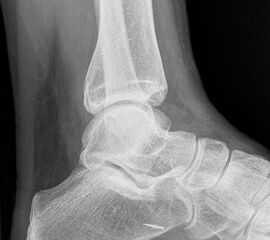

Sprunggelenk lateral ohne Belastung

Positionierung:

• Patient liegt auf dem Rücken und dreht den Fuß des aufzunehmenden Beins so nach innen, dass beide Malleolen genau übereinanderstehen.

• Die laterale Fuss-Seite liegt auf der Kassette, das Sprunggelenk ist 90° angewinkelt.

• Der Zentralstrahl wird zentral auf das Sprunggelenk gerichtet.

Kennzeichen des Röntgenbildes:

• Oberes und unteres Sprunggelenk sind rein seitlich abgebildet, inklusive Kalkaneus.

• Die Malleolen kommen übereinander zu liegen.

• Tibiagelenkfläche und Talusrolle werden exakt seitlich dargestellt, es kommt zu keinen Doppelkonturen.

• Die Fibula projiziert sich ins mittlere bis hintere Drittel der Tibiagelenkfläche.

• Die vordere und hintere Tibiakante, das Chopart-Gelenk und das Subtalargelenk kommen zur Darstellung.

• Das proximale Ende des Os metatarsale V ist mit abgebildet.

• Der Weichteilmantel (Achillessehne) ist erkennbar.

Besondere Bemerkungen zum Beispielbild:

• Patient mit anamnestisch chronischer OSG Instabilität.

• Ventral der Tibia findet sich ein abgebrochener Osteophyt.

Zur Vollansicht und zum Lesen der Bildbeschreibung bitte die Bilder anklicken.